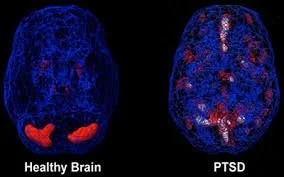

Take a look at this second image. What do you see?

A healthy brain glows evenly. Its systems communicate with one another: emotion, memory, and reason moving in quiet harmony. It can rise to meet stress, then settle back into rest once the threat has passed. People with healthy brains worry about ordinary things: what colour to paint the bedroom walls, for example.

A brain damaged by PTSD cannot comprehend stress at that scale. For us, stress does not mean inconvenience or indecision, it means survival. Worst case scenario. Life or death. Trauma. Fight, flight, or freeze. This image shows how different a PTSD brain is compared to an ordinary brain. Dimmer in some places. Scattered. Uneven. Certain regions burn too brightly, locked in vigilance, while others grow quiet. An organ meant to function as a single, integrated whole becomes divided. One part remains on guard in the past, while the present struggles to be fully inhabited. What you see here is survival etched into biology.

At last, we see proof of what survivors have been saying all along: PTSD alters the brain itself. Those who live with this injury are not “dramatic” by choice. They do not overreact for attention or effect. Their responses are involuntary, driven by a nervous system shaped by trauma. They prepare for the worst-case-scenario not out of paranoia, but because to their nervous system, the worst has already happened — and is expected to happen again. In fact, for those who have endured repeated trauma, this state can become all they have ever known; danger becomes familiar, even routine. What ends up feeling strange to them, is not the vigilance itself, but witnessing others live lives that appear untouched by trauma. The idea of a “normal” life, one without constant threat, can feel confusing, even unreal, to the PTSD brain. It does not align with what the body has learned to expect. When this reality is misunderstood or dismissed, the expectations placed on survivors become not just unfair, but illogical. To demand otherwise would be like telling someone with epilepsy to simply stop having seizures — as though willpower alone could override a neurological injury.